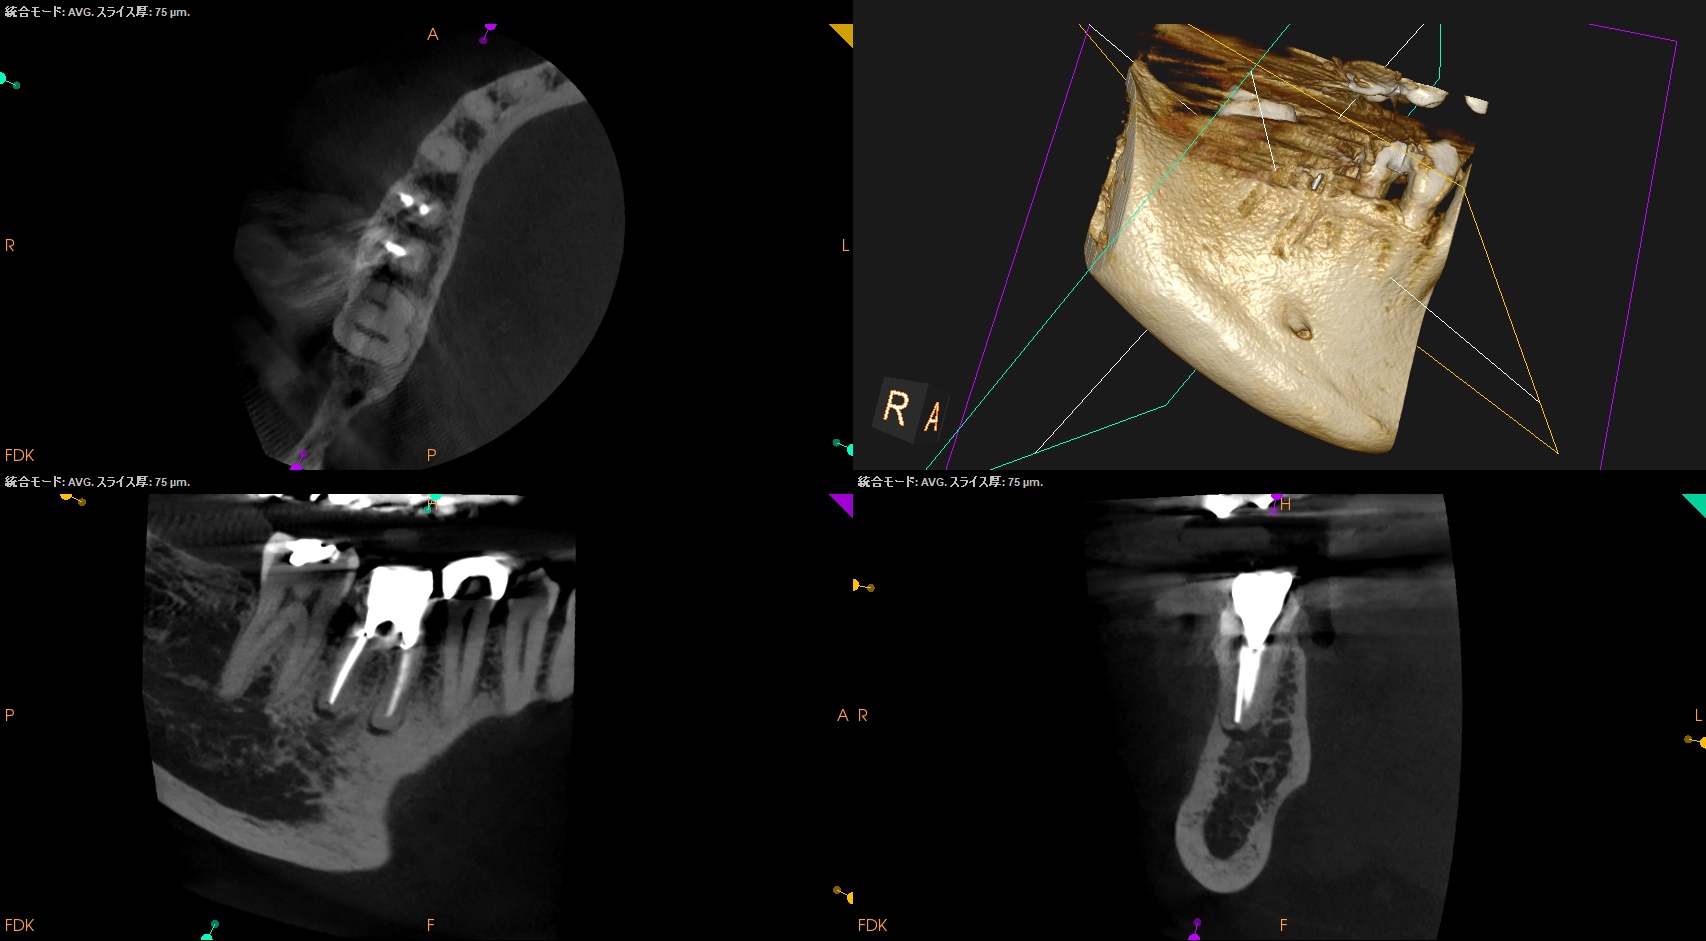

CBCT(2025.10.15)

#30 MB

#30 ML

#30 D

歯内療法学的診断(2025.10.15)

Pulp Dx: Previously treated

Periapical Dx: Asymptomatic apical periodontitis

Recommended Tx: Re-RCT+Core build up